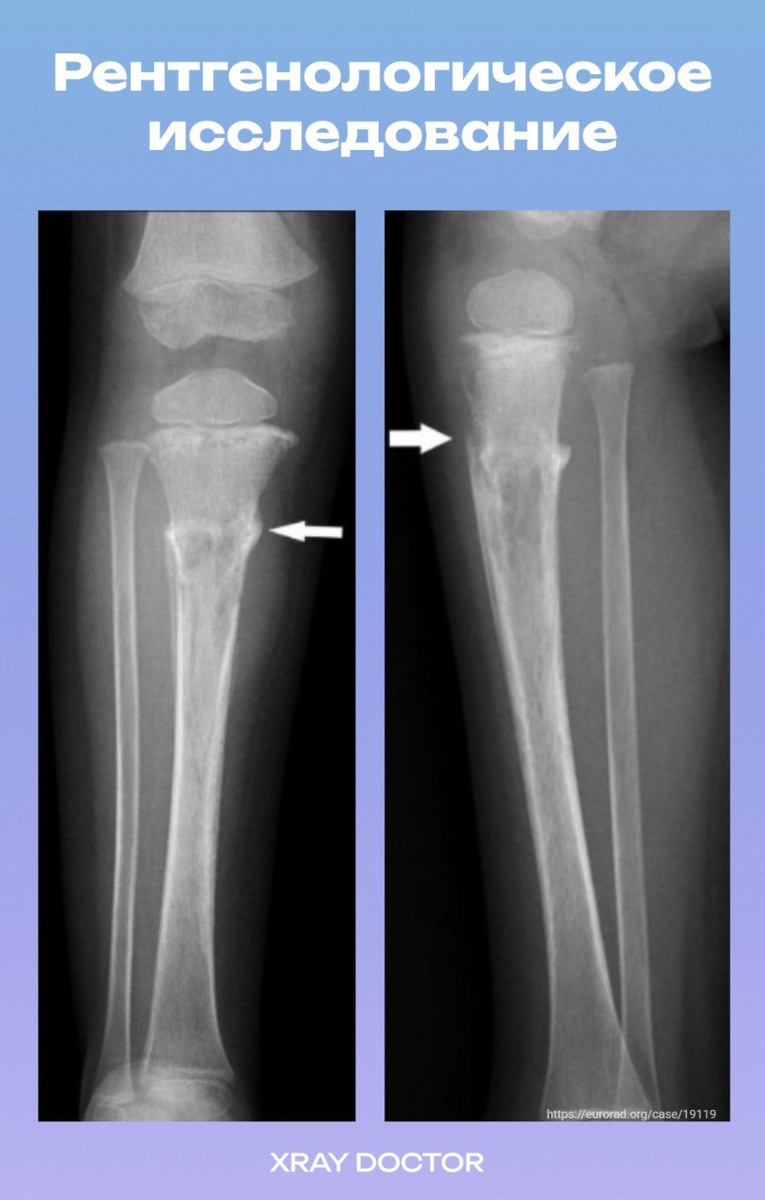

✅Рентгенография показала неоднородное смешанное остеолитико-склеротическое поражение с широкой переходной зоной в проксимальном отделе диафиза большеберцовой кости. В кортикальном слое был обнаружен поперечный патологический перелом, прерывистая пластинчатая реакция надкостницы и отёк мягких тканей.